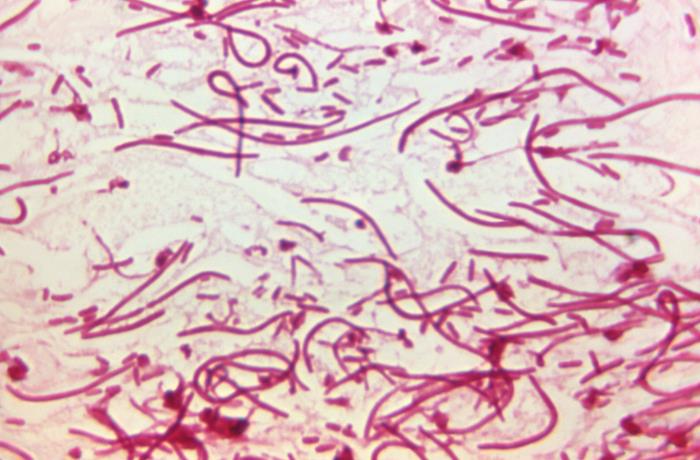

在生物顯微鏡下,痢疾桿菌為短桿狀或圓形,直徑約為0.5微米,長(zhǎng)度約為1 ~ 3微米,菌體被一層薄的肽聚糖壁包裹,菌體表面有許多菌毛。

痢疾桿菌經(jīng)革蘭染色后呈紅色,屬于革蘭氏陰性菌。

綜上所述,通過(guò)生物顯微鏡用于觀察痢疾桿菌的形態(tài)特征,是痢疾桿菌診斷的關(guān)鍵工具之一,通過(guò)顯微鏡下的形態(tài)和染色特性可輔助確認(rèn)痢疾桿菌感染。